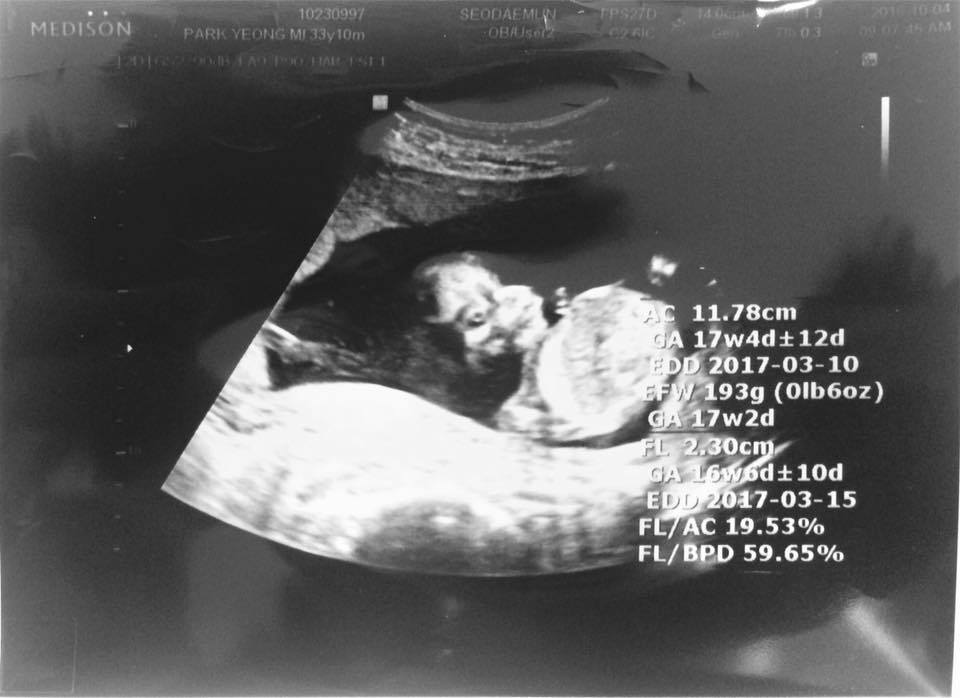

병원에서 초음파로 먼 흑백의 바다를 보다가 우연히, 아가, 네가 하품을 하는 걸 보았다.

우린 백번, 천 번 돌려보며 음파음마엄마들에게 영상을 보냈다.

예쁘다며 난리였다.

아무리봐도, 고래를 닮았다고 생각했다.

젖을 먹는 고래를.